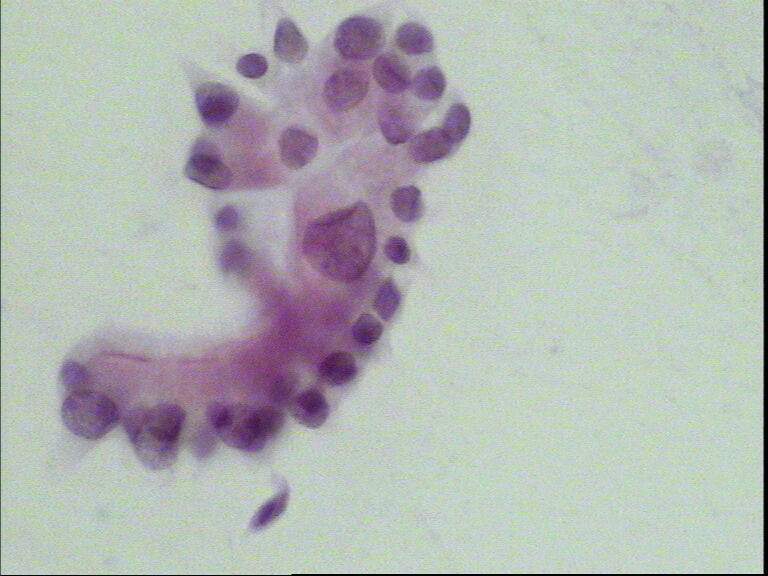

男性,65岁,支气管灌洗液,肝癌术后

• 男性,65岁,支气管灌洗液,肝癌术后图1

个别异型细胞,癌细胞不能排除。

个别细胞有异常  报可疑吧

打少数核异质细胞足够了。